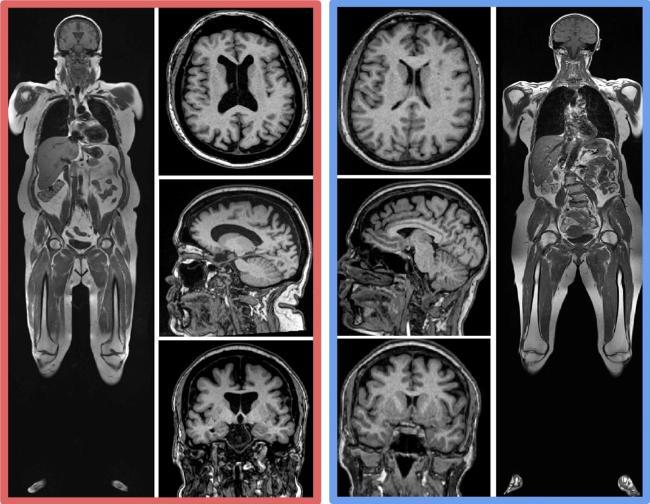

The results from this large data set were contextualized down to individual examples when comparing two MRI scans in two participants from the study with the same age and sex:

“Magnetic resonance imaging that encompassed the abdomen and head helped us determine both higher visceral and subcutaneous abdominal fat volume predicts loss of brain volume, a key metric of brain health,” said lead study author Cyrus A. Raji, MD, PhD, of Washington University in St. Louis, who collaborated with the research team at the Pacific Brain Health Center.

For the study, 10,001 healthy people aged 18 to 90 years old had whole body scans with MR imaging machines. Deep learning was used to determine the volume of 96 brain regions. The same scan also was used to find the amount of visceral and subcutaneous abdominal fat on the scans. Then researchers looked to see if there was a link between these types of abdominal fat and brain volume.